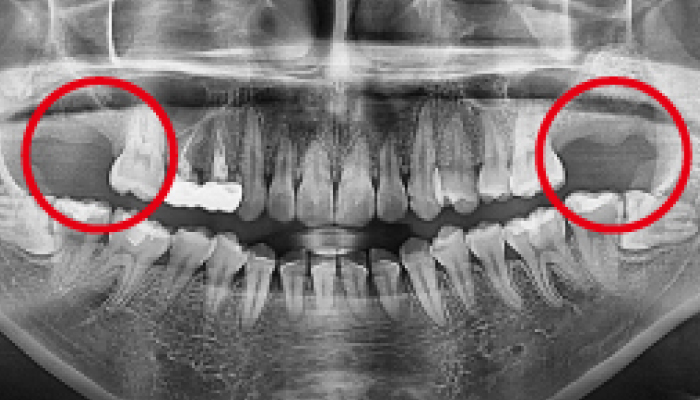

Before

로그인 후 이용해주세요

After

매복 사랑니 발치

이OO님 전후사진 / 치료 기간 : 30분 / 당일 사랑니 발치

Before

로그인 후 이용해주세요

After

매복 사랑니 발치

이OO님 전후사진 / 치료 기간 : 30분 / 당일 사랑니 발치

-

Before

로그인 후 이용해주세요

After

매복 사랑니 발치

심OO님 전후사진 / 치료 기간 : 30분 / 당일 사랑니 발치

-

Before

로그인 후 이용해주세요

After

매복 사랑니 발치

서OO님 전후사진 / 치료 기간 : 30분 / 당일 사랑니 발치

-

Before

로그인 후 이용해주세요

After

매복 사랑니 발치

김OO님 전후사진 / 치료 기간 : 30분 / 당일 사랑니 발치

-

Before

로그인 후 이용해주세요

After

당일 사랑니 발치

이OO님 전후사진 / 치료 기간 : 30분 / 당일 사랑니 발치

-

Before

로그인 후 이용해주세요

After

매복 사랑니 발치

노OO님 전후사진 / 치료 기간 : 30분 / 당일 사랑니 발치